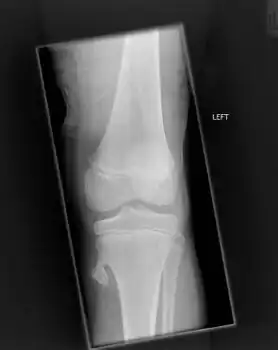

Osteochondroma arising from the thigh bone, near the knee

Osteochondroma arising from the large long bone of lower leg, near the knee